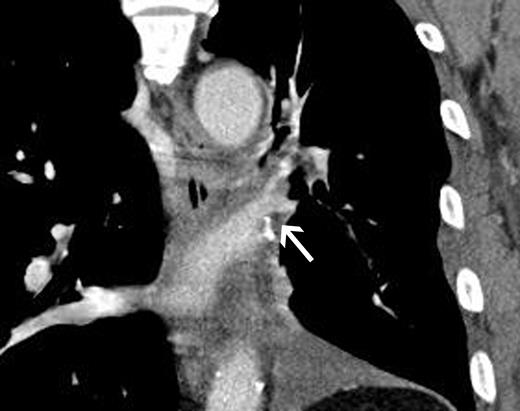

Thoracoscopic left upper lobectomy was performed. The common trunk of the left pulmonary vein was misidentified as a superior pulmonary vein until incidental transection with an endostapler during port access surgery. The caliber change between the common trunk and the inferior pulmonary vein was marked. Thoracoscopic surgery was converted to open thoracotomy. The left upper bronchus and pulmonary arteries to the left upper lobe were transected with endostaplers, and the common trunk of the pulmonary vein was left intact. The left main pulmonary artery was then clamped under intravenous heparin injection to achieve an activated coagulation time of 200 s. Annuloplasty of the inferior pulmonary vein was completed during intermittent declamping of the left pulmonary artery. The orifice of the inferior pulmonary vein was augmented by a cuff technique using an orifice of the superior pulmonary vein, as shown in Fig. 1. The staples on the stump of the left common pulmonary vein on the atrial side were removed to adjust the augmented orifice of the left inferior pulmonary vein under partial clamping of the left atrium following pericardiectomy. End-to-end anastomosis was completed using running sutures with a 4-0 polypropylene thread. The anticoagulant therapy was continued until 2 months after surgery. The postoperative course was uneventful, and the patient was discharged on postoperative day 14. A pathologic study showed stage T1N2M0 small-cell carcinoma as categorized by the 7th edition of the UICC classification. Postoperative enhanced CT demonstrated successful reconstruction of the left common trunk (Fig. 2).

Postoperative enhanced CT showing (frontal view) successful reconstruction of an inferior pulmonary vein (arrow).